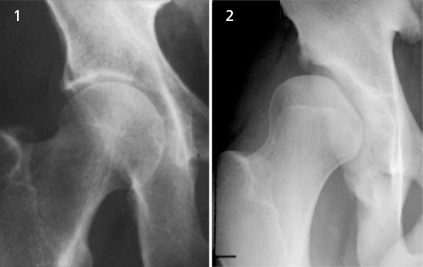

Second, anatomy and genetics do play a role. I never like to bear bad news, but some of you aren’t meant for breaststroke (at least a wide breaststroke kick) and you may not find this out until maturity. Scientific literature is finding out some people have deeper hip sockets than others. A deep hip socket prevents the amount of hip internal range of motion and breaststroke kick width. Japanese have shallower hip sockets, which is potentially why they have a higher rate of elite breaststroke swimmers.

Another anatomical factor is the angle of head of the thigh, the angle of inclination. If you have a smaller angle of inclination, you likely can perform more hip range of motion for breaststroke. Once again, the anatomy plays a role, as different anatomy allows greater motion. If you have a deep hip socket with a large angle of inclination, you pelvis bones likely run into each other, preventing a wide breaststroke kick.